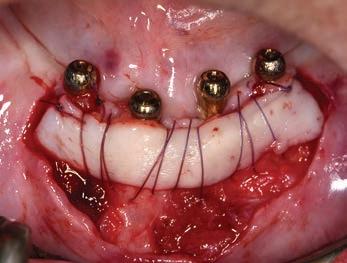

The third step of the treatment consisted of the crown lengthening, necessary to expose an adequate part of the root to obtain, after healing, the correct adhesion of the composite for the pre-prosthetic restoration and the successive prosthetic rehabilitation.

After the surgical flap elevation of the tissue and the bone remodeling, the flap was repositioned apically and sutured with a vertical mattress suture anchored in the periosteum (Figs. 5-6). The suture was removed after 7 days (Fig. 7).

glass fibre Figure 3: Root canal therapy completed under proper isolation. Figure 4: Radiography of completed root canal therapy and reconstruction made completely in glass hybrid cement. Figure 5: Clinical crown lengthening with a minimally invasive technique without mesial and distal discharges. Note the proximity of the reconstruction in glass hybrid material to the mesial bone ridge. Figure 6: Suture at the end of surgical therapy. It was left in place for 7 days Figure 7: Suture removal at 7 days. Post-surgical edema is still present.